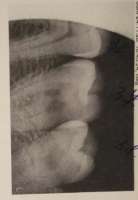

111.jpg 47Кб, 267x351

Вопросы к реальным стоматологам. Если тут таковые имеются, конечно.

Весной от зуба (шестерка) кусок откололся, задняя часть, воспаления и чувствительности при этом не было. Пульпа живая осталась, заделали, прошло как лечение глубокого кариеса. Поначалу все нормально было, но летом появилась небольшая чувствительность к холодному. Сразу скажу, что тверже огурца я ничего не ел, орехи не грыз. Ну, я с тех времен на всякий случай стал жевать другой стороной, мало ли что-то недозажило, этим зубом уже по привычке почти не пользовался. Внезапно неделю назад этот зуб адово разболелся, не дотронуться. Именно сам зуб, не десна. Теперь от холодного наоборот было легче, а от теплого и горячего - словно паяльником в рот тычут. На пикр текущий рентген этого зуба. Внешне, на глаз, зуб целый. На мой вопрос, какого хрена и не подпадает ли это под гарантию, врач осмотрела зуб и обвинила меня в том что это моя вина, что мой организм не справился, какой-то там дентин вокруг пульпы не нарос, и якобы предупреждала что даже если такое случилось бы на следующий день еще весной, то никакой ее ответственности за это тут нет. Типа вот ренгген, пломба стоит на месте, все заебись, это чисто моя вина. Не согласен - жалуйся, доказывай как хочешь. То есть попадаю на удаление пульпы и чистку-пломбировку каналов. Моя же версия состоит в том, что где-то образовалась микротрещина или иной путь к пульпе, от чего она и подыхает. То что оно само по себе взяло и сдохло, спустя столько времени - на мой взгляд сомнительно.

Вопросы таковы:

1) Кто прав, на ваш взгляд? С момента ремонта зуба прошло ~полгода, должна ли клиника нести ответственность за осложнения?

2) Лично я на рентгене не вижу отличий от здоровых зубов, можно ли тут что-то понять о состоянии пульпы и масштабе воспаления?

3) Мне назначено на пятницу, но на данный момент зубу сильно полегчало. Думаю, еще пару дней и боль полностью пройдет. Правда ли, что все-равно обязательно удалять пульпу/нерв в данном случае, т.к. будет гнить и в будущем воспалится десна? Как вообще понять, что нерв реально сдох и разлагается?